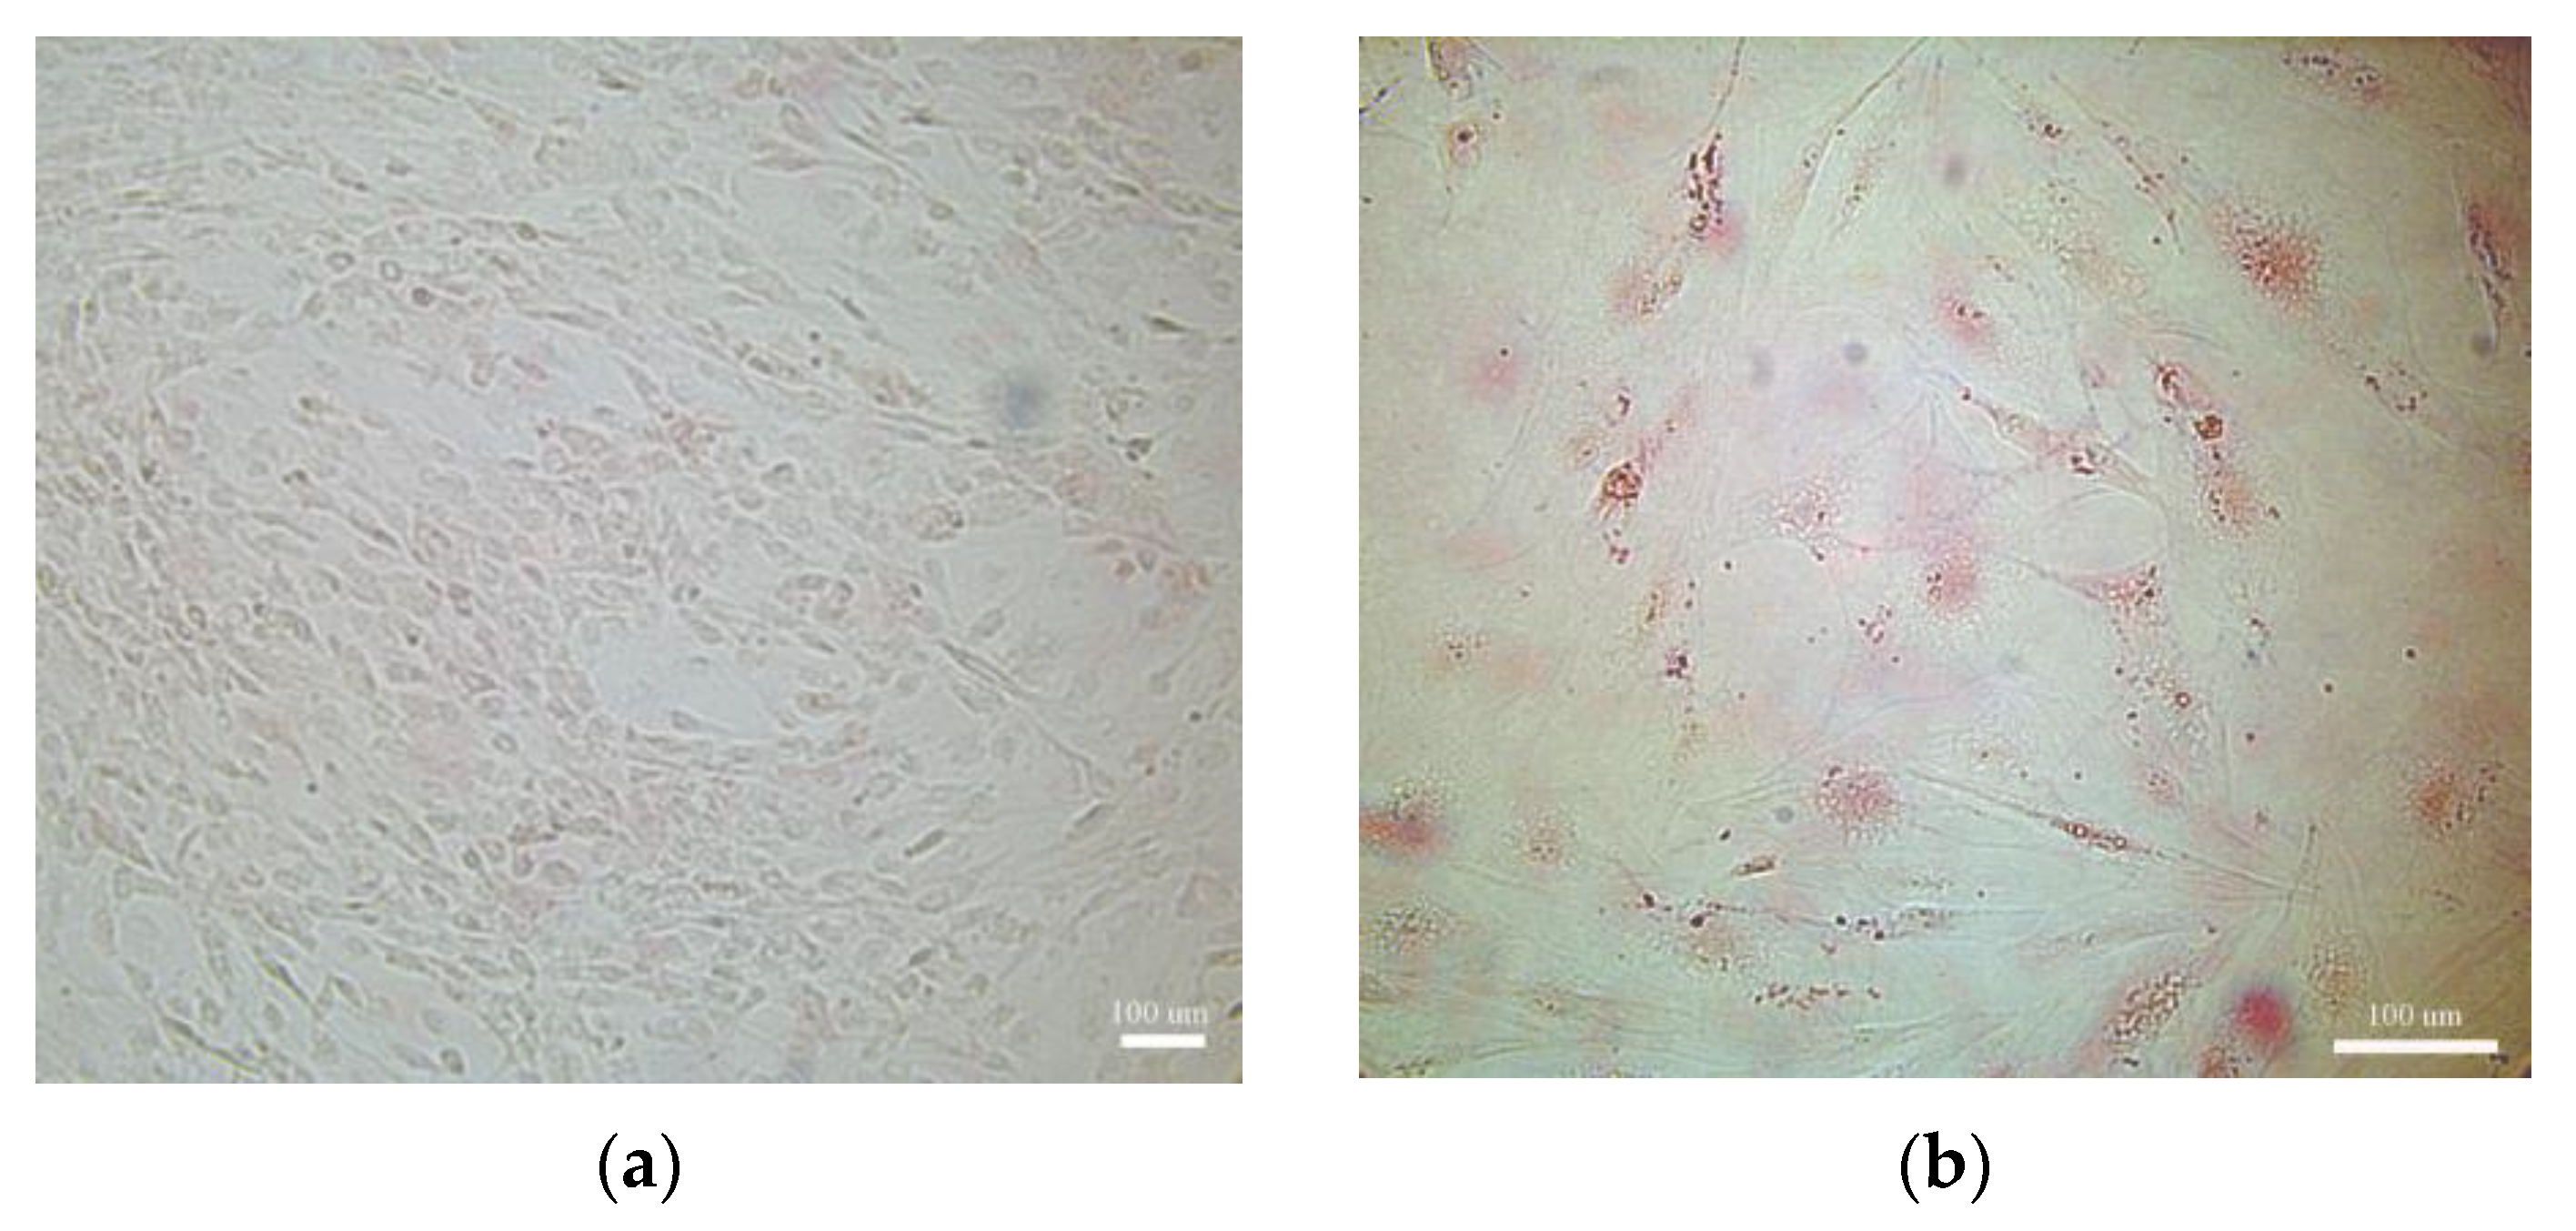

2.1. Inflammation Impairs Adipose Tissue Function Affecting Adipose Cell Maturation

4.2.2. Cell Culture: Adipocyte, Adipose Mesenchymal Stem Cells (ASCs), and Adipose Differentiation